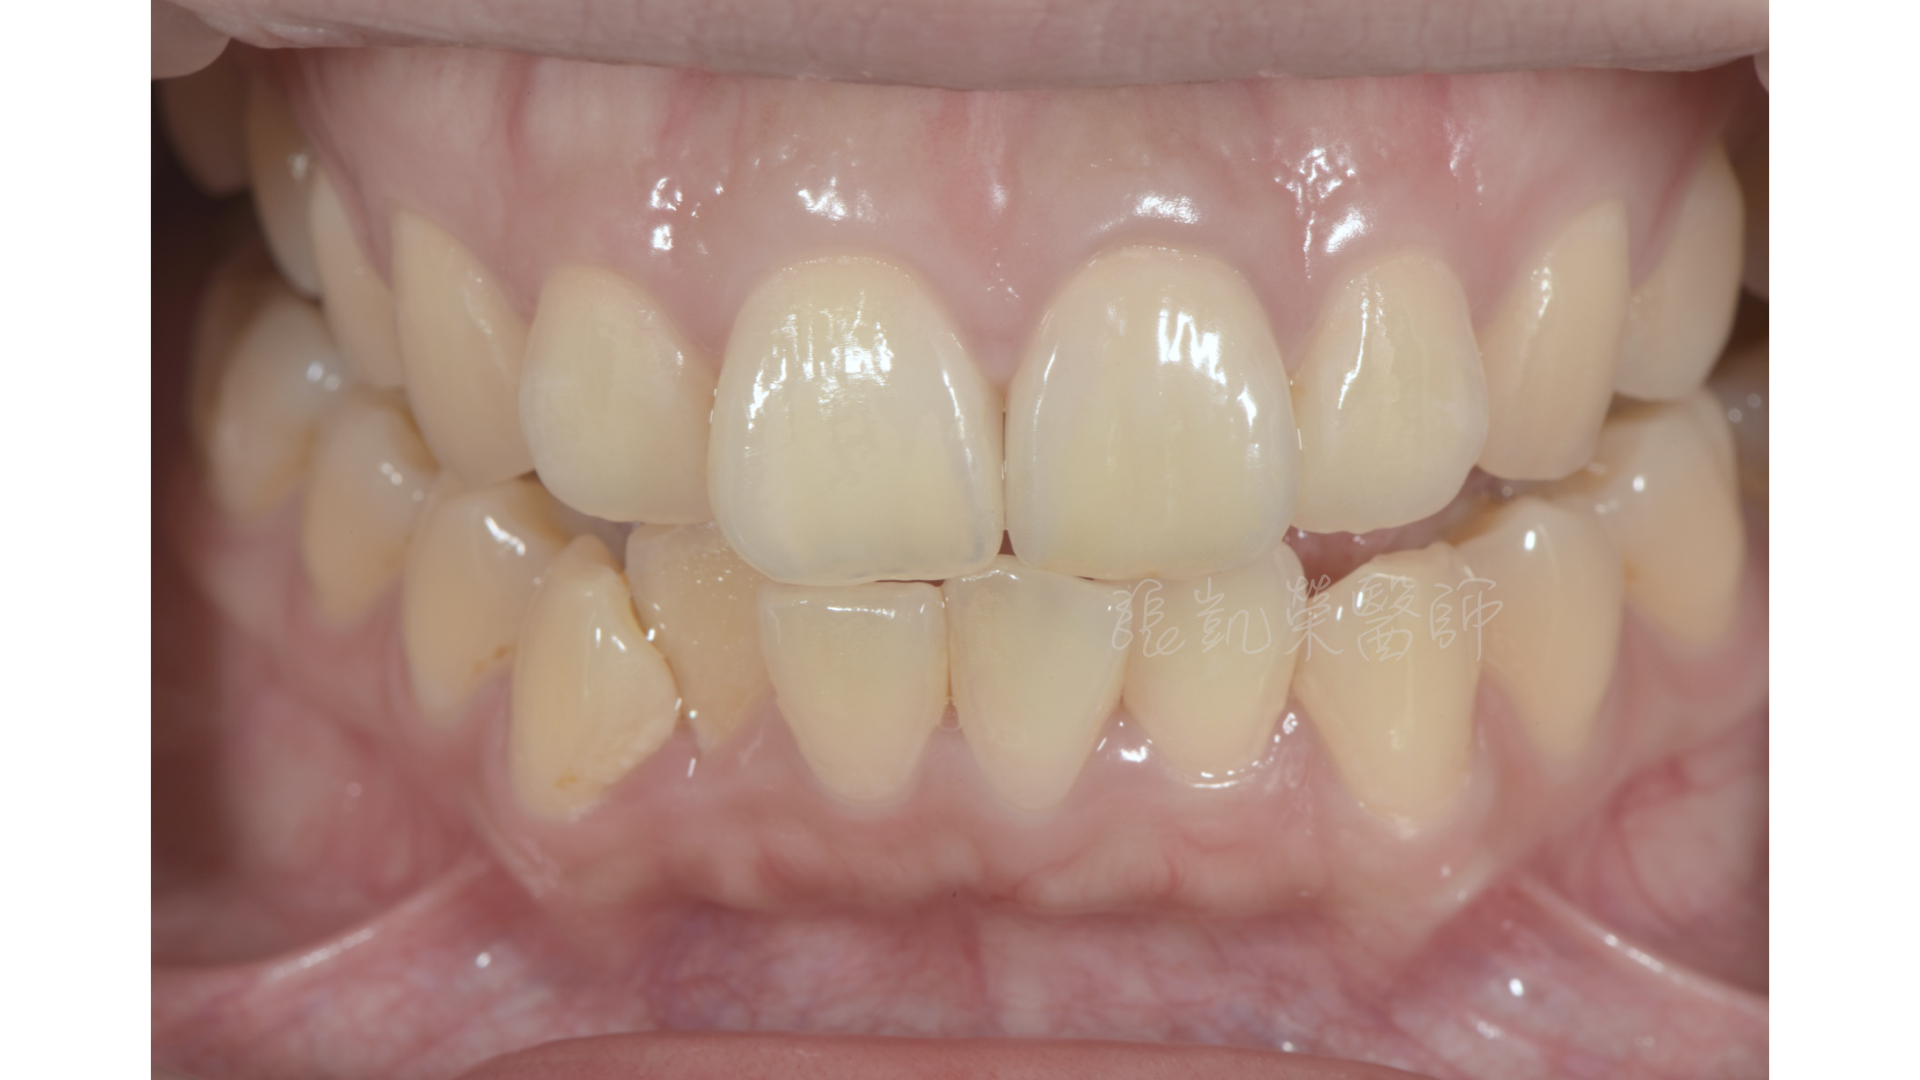

臨時假牙